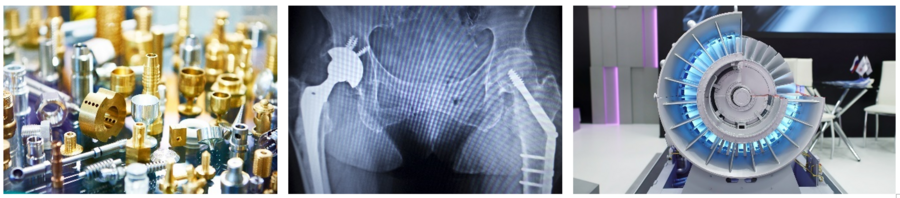

Nichteisenwerkstoffe sind eine zentrale Werkstoffgruppe moderner Technologien und finden in zahlreichen Anwendungsbereichen Verwendung – von der Luft- und Raumfahrt (Turbinenschaufeln aus Ni-Basiswerkstoffen) über den Fahrzeugbau (Leichtbaustrukturen aus Al- und Mg-Basiswerkstoffen), die Medizintechnik (Ti-Basiswerkstoffe) bis hin zur Elektronik (Cu-, CuW, CuCr). In der Vorlesung "Nichteisenwerkstoffe" widmen wir uns eingehend den besonderen Eigenschaften und Verarbeitungsmethoden dieser Materialien, die aufgrund ihrer spezifischen Merkmale oft als Alternative zu eisenbasierten Werkstoffen gewählt werden. Der Kurs vermittelt grundlegende Kenntnisse zu den wichtigsten nicht-eisenhaltigen Metallen wie Aluminium, Kupfer, Titan, Nickel und Magnesium sowie zu innovativen Verbundwerkstoffen. Dabei werden sowohl die klassischen als auch die modernen Herstellungstechnologien beleuchtet. Es werden die charakteristischen physikalischen, mechanische und chemische Eigenschaften dieser Werkstoffe und deren Verarbeitungstechnologien behandelt.